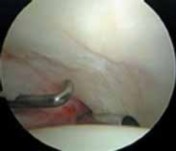

1. Most symptomatic labral tears are managed with selective débridement of the damaged portion ( TECH FIG 1).

2.

Emphasis is given to preserving healthy tissue, because removal of normal labrum can lead to poorer results.

3.

A complete joint survey is performed with thorough inspection and palpation of the labrum, identifying its damaged portion.

4.

Most labral resection is carried out with a power shaver, debulking the damaged tissue.

1.

Hand instruments and an arthroscopic knife may aid in this resection.

It is important to preserve the healthy tissue but create a stable transition zone when completing the débridement.

A radiofrequency device is especially useful for this because of the limited maneuverability imposed by the architecture of the joint.

Diseased tissue has an increased water content and responds selectively to the thermal device.

TECHNIQUES A B TECH FIG 1 • Arthroscopic view of a right hip from the anterior portal. A. A fragmented labral tear with degeneration within its substance is identified. B. Débridement is initiated with the power shaver. C. A portion of the comminuted labral tear is conservatively stabilized with a radiofrequency probe. D. The damaged portion has been removed, preserving the healthy substance of the C D labrum. LABRAL REPAIR